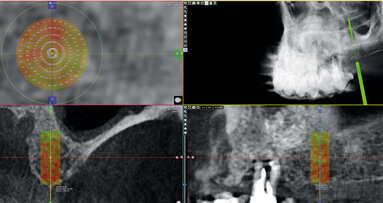

Hlavními indikacemi, v nichž jsme tuto technologii použili, byly v dentoalveolární chirurgii chirurgické extrakce, fenestrace a tunelizace retinovaných zubů, exstirpace cyst s eventuální retrográdní endodoncií a kortikotomie k urychlení ortodontické léčby. V implantologii jsme prováděli sinus lift, preparace lože implantátu, rozšíření alveolárního výběžku horní i dolní čelisti a odběr kostních štěpů, a v chirurgii maxilofaciální osteogenní distrakce, pomocné osteotomie v ortognátní chirurgii, deliberace nervus alveolaris inferior k jeho následné mikrochirurgické rekonstrukci a v současné době i široké spektrum výkonů otevřené chirurgie temporomandibulárního kloubu.

Piezochirurgie představuje v kostní chirurgii k měkkým tkáním dostatečně šetrnou techniku založenou na ultrazvukových mikrovibracích. Vyvinuta byla na základě myšlenky italského parodontologa, dentoalveolárního chirurga a implantologa Tomaso Vercellotti v roce 1998 a klinické zkoušky na území České republiky byly zahájeny v roce 2002. Po celou dobu existence této technologie docházelo k jejímu vývoji, takže v současné době je velmi efektivní a v mnoha směrech překonává hranice tradičních chirurgických technik. Četné histologické práce o hojení kostních ran a utváření kostí na pokusných zvířatech ukázaly, že odpověď tkání je v případě použití piezochirurgie příznivější ve srovnání s tradičními technikami řezání kostí za použití rotačních tvrdokovových nebo diamantových nástrojů32. Dokazuje to i závěr našeho experimentu provedeného v roce 2010, kdy jsme vyšetřovali histologicky odpověď naléhající mozkové tkáně pokusných zvířat, u nichž jsme preparovali kalvu v blízkosti jedné z hemisfér rotačním nástrojem a na straně druhé pomocí piezochirurgie17. Porovnáváme-li histologicky kostní okraje fragmentů získaných během operace provedené ultrazvukovým přístrojem a klasickou pilkou, nevykazuje mikroskopické vyšetření tkáně preparované pomocí piezochirurgie znaky nekrózy; na kostním povrchu jsou zachovány osteocyty s vitálními jádry. Tím je chráněna i vitalita zubu v blízkosti preparace19.